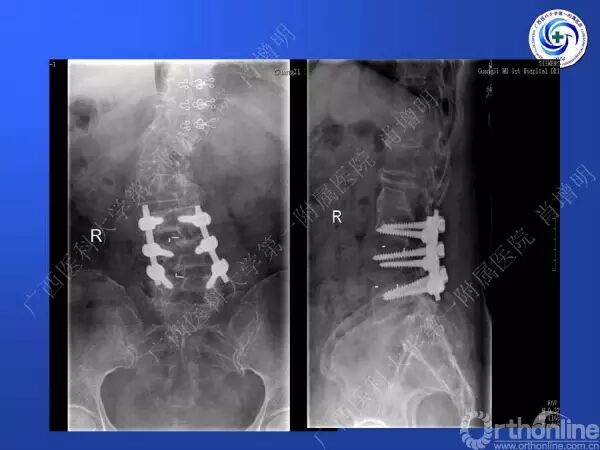

退变性脊柱侧凸多发于50岁以上的中老年群体,是现代常见的老年疾病。多年来,针对该病的临床研究一直没有停步,广西医科大学第一附属医院肖增明教授细致地介绍了该病的诊疗进展。